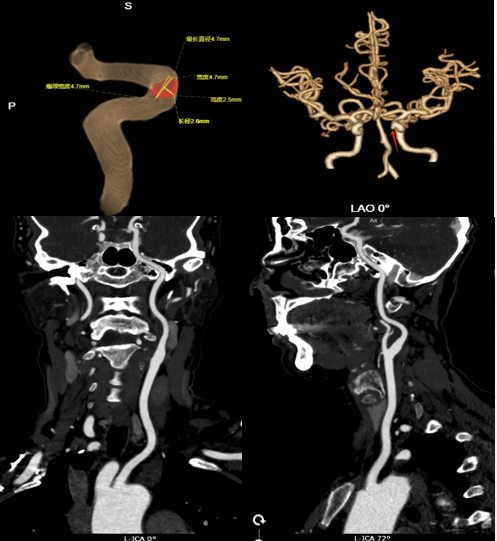

CTA 结果显示:左侧颈内动脉 C5 段确实有一处瘤样凸起,小动脉瘤可能性大。更令人惊叹的是,中心采用的 AI 智能测量系统进一步精准勾勒出动脉瘤的形态、瘤颈宽度与载瘤动脉的关系,为后续治疗方案的制定提供了关键依据。

CTA(CT 血管造影):通过静脉注射碘对比剂,利用 CT 快速扫描获取血管三维图像。其空间分辨率高,能清晰显示动脉瘤的形态、位置、与周围骨骼和脑组织的关系,是确诊和术前评估的首选。